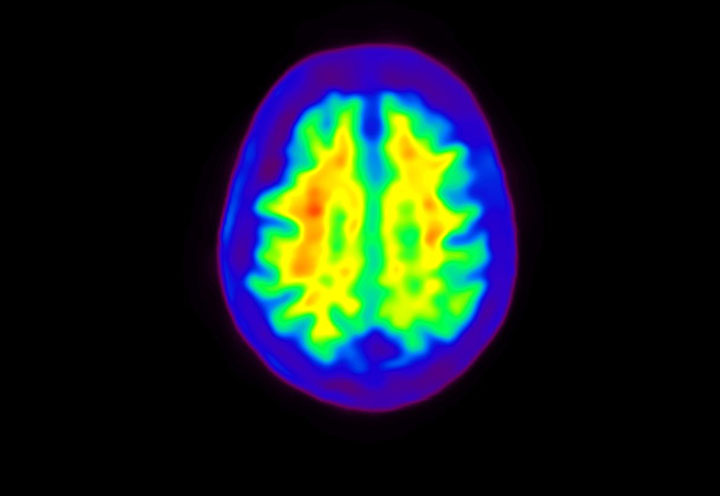

Head / Case4 : Amyloid

Axial

Courtesy : Kindai University Hospital

- Imaging protocol

- Injected dose: 3.21 MBq/kg, 18F-Flutemetamol

- Uptake time: 100 minutes

- Scan time: 20 minutes